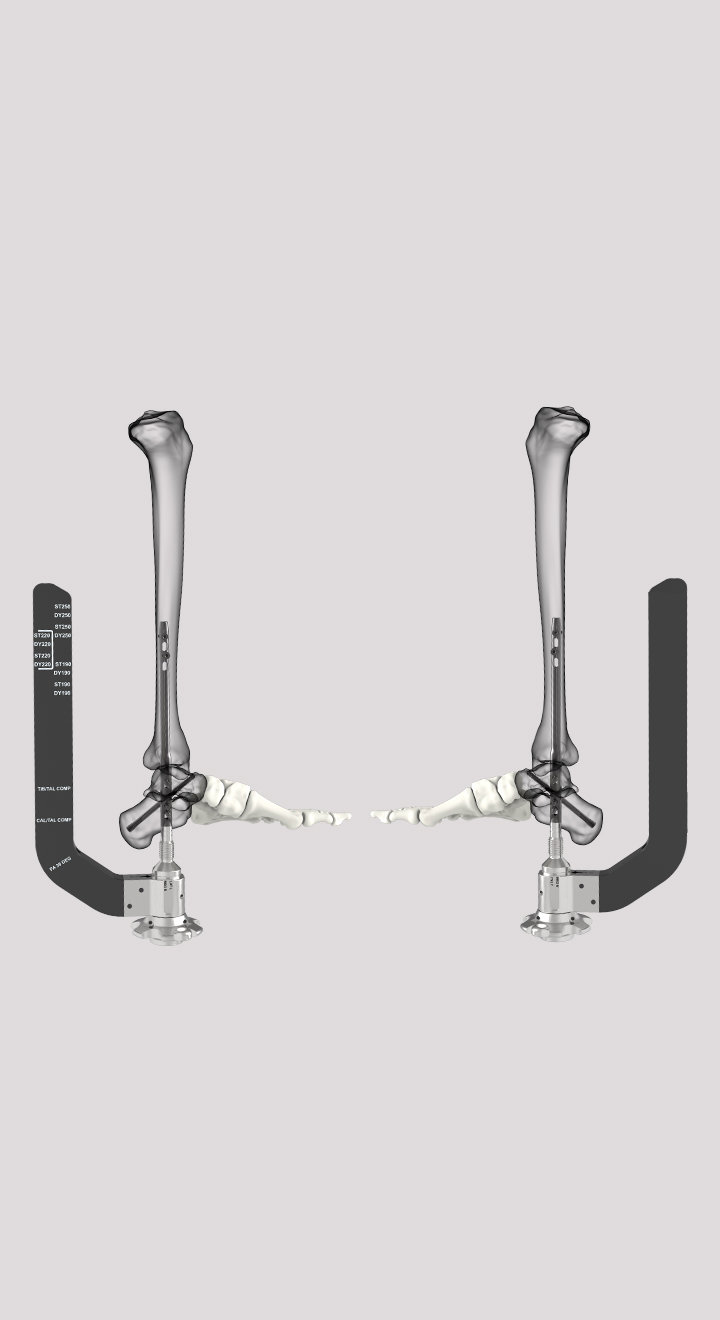

SUCCESSION® TTC Nail System

The SUCCESSION® TTC Nail System provides the surgeon with greater control, allowing for customized treatment based on each patient’s specific needs